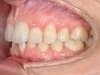

Cas N°6 : Description

Correction majeure des deux arcades dentaires liée à une mandibule rétrusive

Avant

Après